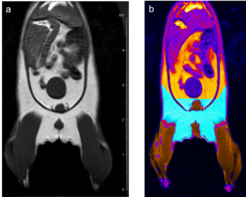

Fat, muscle, tissue-free fluids, and bones generate different signals in response to various radio frequency pulses at distinct magnetic fields, due to their different relaxation properties. We perform MRI studies on mouse using T1-weighted multi-slice-multi-echo (MSME) pulse sequences and analyze the volume of muscle and fat in a well defined and comparable area of the mouse Fig. 6.

Fig. 6: Determination of body fat in mouse. (a) A MSME sequence with a repetition time of 452 ms, echo time of 8.6 ms, field of view 7.0x7.0 cm2 covering the entire body and lower legs, a matrix of 512x256 and slice thickness of 1.0 mm was used to acquire 20 coronal slices with1.0 mm slice thickness and 1.0 mm interslice distance. (b) After evaluation the region in cyan represents the quantified fat and the region in brown the quantified muscle volume.